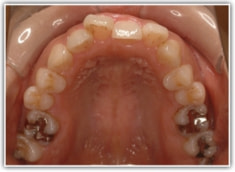

上顎前突ケース

治療法:表の矯正(T21ブラケット)

治療前